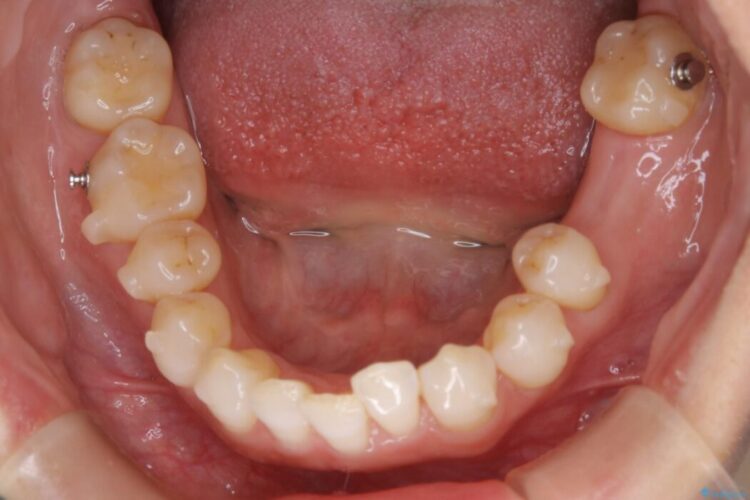

悪くなっている歯の放置はできないと判断しましたので、患者様と様々な治療プランを相談した上で、最終的に該当の歯は抜歯をして噛み合わせを改善し、その後インビザラインでの矯正治療を行うこととしました。

治療後について

噛み合わせも改善され、一番最初の目的であった歯列もきれいに整いご満足いただけました。